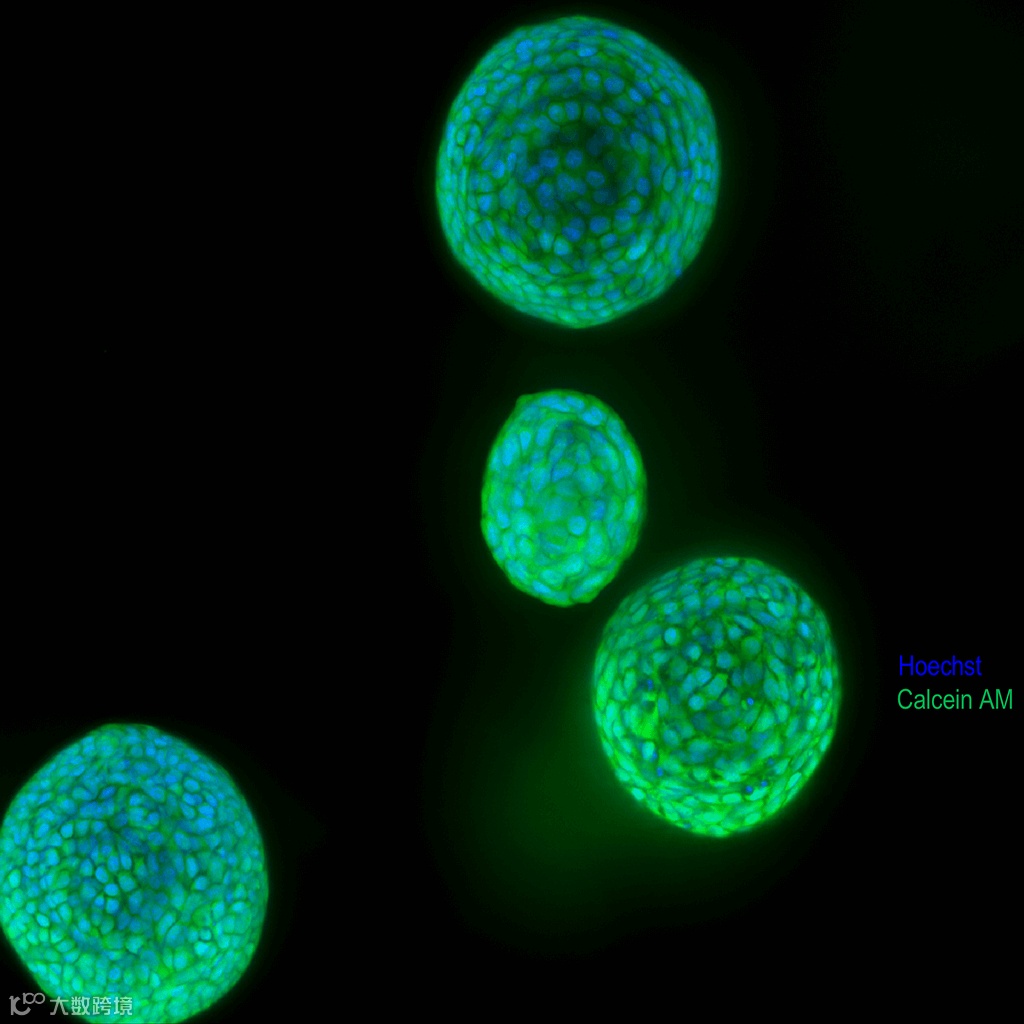

共聚焦成像,如带有高性能激光和水浸物镜的 ImageXpress® Confocal HT.ai 智能化共聚焦高内涵成像分析系统,对于捕获 3D 生物检测分析的复杂性尤其有用。与典型细胞球具有固体的外观和有限的透光能力不同,3D 类器官具有中空外观,内部有腔室或空洞,因此更容易被光线穿过,从而允许对嵌入基质胶的多种微小组织进行“成像”。

当软件在 3D 空间中连接和重构来自多个平面的对象时,高内涵分析工具(如 MetaXpress 或 IN Carta 成像分析软件)能够查找和表征多个对象/类器官,无论它们是 2D 格式(单个平面或最大投影图像)还是 3D 格式。可以描述类器官的直径、体积、形状、特异性标记物或与其他对象之间的距离。

此外,可以确定和测定每个类器官中的单个细胞、细胞核或细胞器。可以对活细胞和死细胞或有特异性标记物的细胞进行计数,同时还能确定各个对象的体积及它们之间的距离。可以计算每个类器官的数值,或计算每个孔的平均数值。

类器官

类器官是三维(3D)多细胞微小组织,旨在更好地模拟人体器官的复杂结构和功能。类器官通常包含细胞的共培养物并显示出高度的自组装性,因此与传统的二维(2D)细胞培养物相比,可以更好地显示复杂的体内细胞应答以及相互作用。

肺类器官细胞图像库